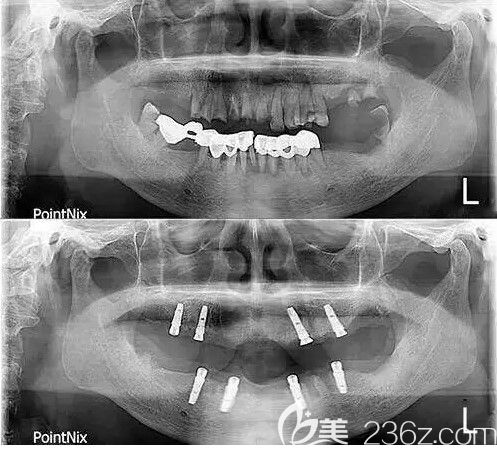

種牙前和種牙后的CT片,用了4顆種植體彌補了我多年來的腐爛牙:↓↓